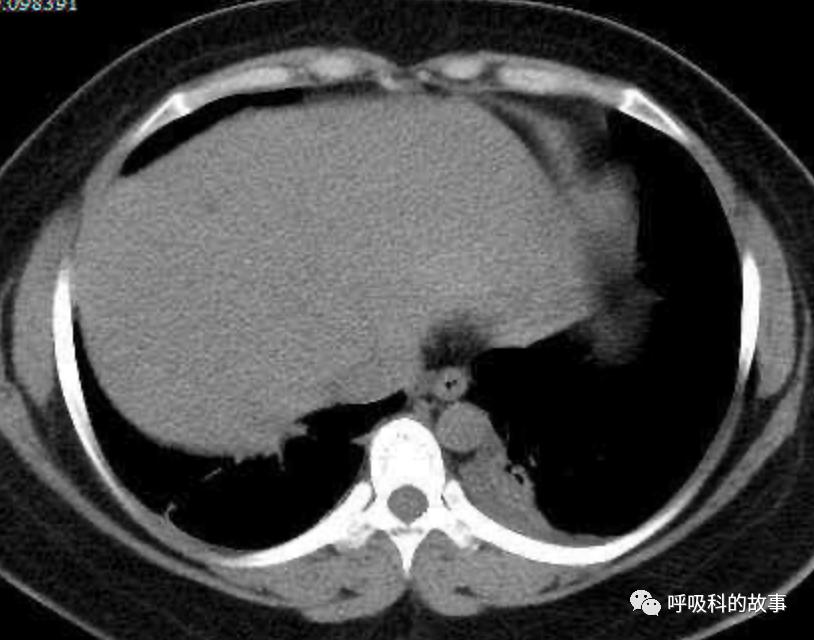

患者发热后行胸部CT检查(6月21日,住院第13天),可见两下肺有条片影,当时考虑是肺炎引起的发热。

可是在6月26日(往院第18天)仍持续发热的情况下复查肺部CT,肺部病灶已明显吸收了。那么患者发热的原因到底是什么呢?为什么患者高热的情况下血白细胞不升反降,C反应蛋白也没有明显增高?这个时候消化科医生也迷茫了,这可怎么办?于是请感染科和呼吸科医生一起会诊,共商计策。